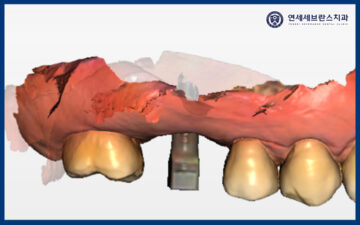

25.12.02

<임플란트 수치 측정 및 보철 작업 시작>

이렇게 약 4개월간의 치유기간을 거친 뒤,

곡반정동임플란트의 수치를 측정해 보니

처음과 다르게 높은 수치로

안정적인 상태를 확인할 수 있었습니다.

그래서 보철 단계로 넘어가

구강 스캐너를 이용해

치아 형태를 정밀하게 촬영하고,

환자분께 자연스럽고 편안하게 맞는

보철물을 제작하기로 했습니다.